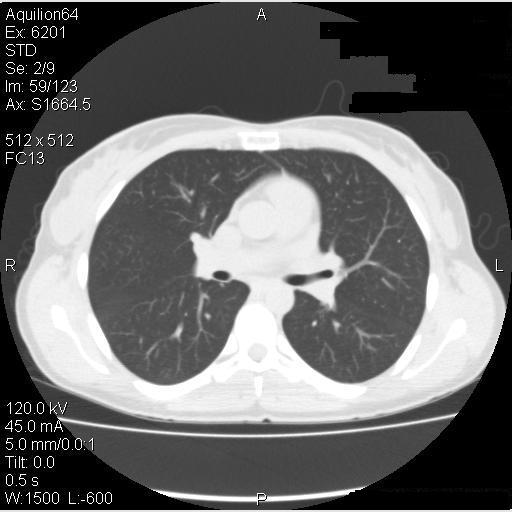

The patient was advised to avoid all possible agents in her environment which could have triggered hypersensitivity pneumonitis – the barn itself, horse-feed and horse-feed supplements, pigeons, and the hot tub. Since she did not have help on the farm she was not able to avoid the barn or feeding the horses but she did stop using the feed supplement and avoided the barn loft. Due to the severity of her symptoms, she was started on prednisone, initially 25 mg per day. She had a marked improvement in her symptoms, with a return to almost normal exercise tolerance and resolution of her pulmonary function abnormalities within a few days. She then returned to her usual activities without recurrence of symptoms although she continued to avoid the horse-feed supplement. Her pulmonary function testing progressively improved (Table 3), and CT scans 2 months and 6 months later also progressively cleared (Figure 5).